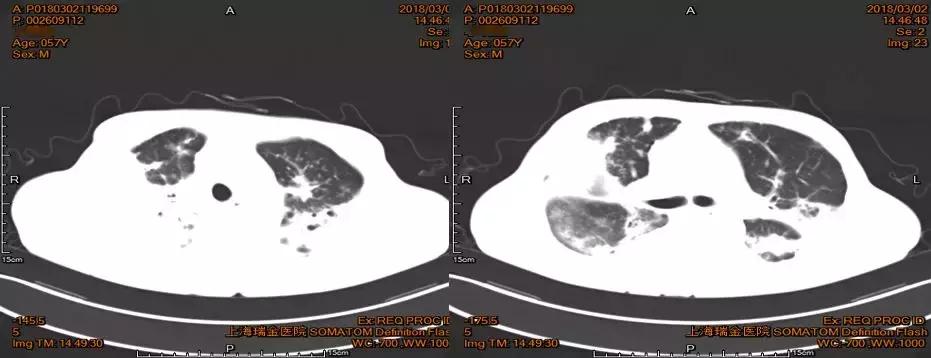

病例三 关注糖尿病合并侵袭性肺曲菌病

患者,中年男性,57岁,货车司机(经常夜里开车)。

现病史:患者20多天前无明显诱因下出现咳嗽、咳黄色黏痰,偶有痰中带血,伴有活动后胸闷、气促,呈进行性加重,伴乏力、纳差,无发热、畏寒,无胸痛、心悸,于2018-01-13日在当地医院就诊。似乎是社区获得性肺炎的临床表现,予以莫西沙星、头孢曲松钠等药物治疗,效果差,查胸部CT发现双肺散在结节状高密度影,内有空洞,病情进展迅速,出现了心功能衰竭、肾功能衰竭、多脏器功能衰竭。既往长期吸烟,有糖尿病,未规范用药,血糖水平不监测。

2018-02-01痰培养曲霉菌生长。

【2018-02-05,上海瑞金医院】痰高通量测序结果显示仅有曲霉菌生长。

2018-03-02日治疗后临床好转,复查胸部CT:多发病灶,多发坏死空洞。

减量后病情反复

糖尿病病人合并肺曲霉菌感染后,对结构的破坏非常明显,而且病程很长。出院后继续规律性口服伏立康唑200mg bid口服,于2018-06-05日伏立康唑减量为100mg bid口服,患者于2018-06-09睡前突发咯血,鲜红色血痰,共八口左右,量约50ml,伴咳嗽加重,又入院进行伏立康唑静脉治疗半个月症状好转。